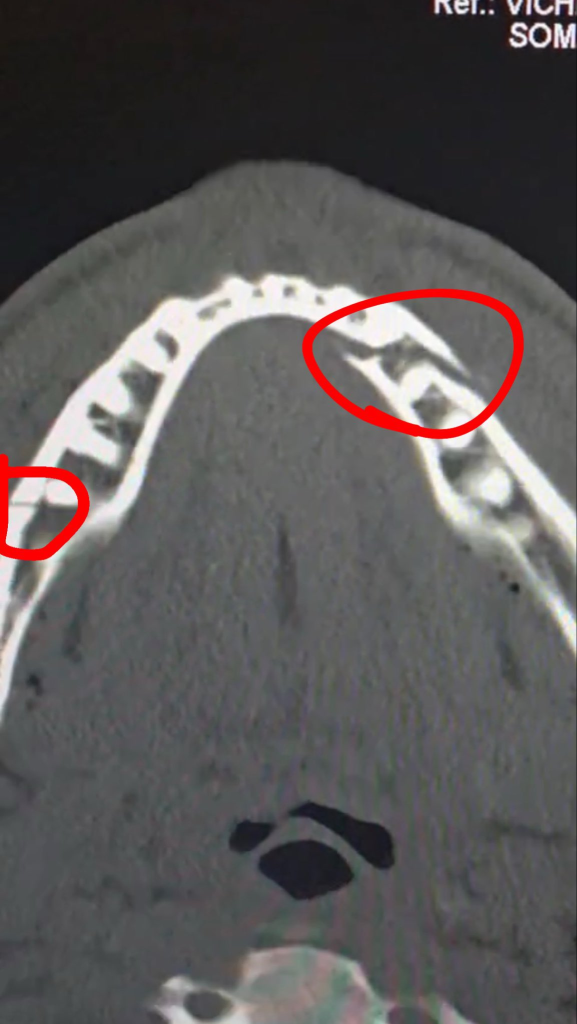

The physical toll of facing a rejuvenated Joshua became evident immediately. Paul was rushed for medical attention, missing the post-fight press conference to undergo emergency surgery. Taking to Instagram to update his millions of followers, Paul shared an X-ray revealing a double fracture along his jawline.

The medical procedure involved fitting two titanium plates to stabilize his jaw and the removal of several teeth dislodged by Joshua’s relentless right hand. Despite the agony, Paul maintained his signature bravado, joking on social media that he could still fight Mexican icon Canelo Alvarez “in 10 days.”